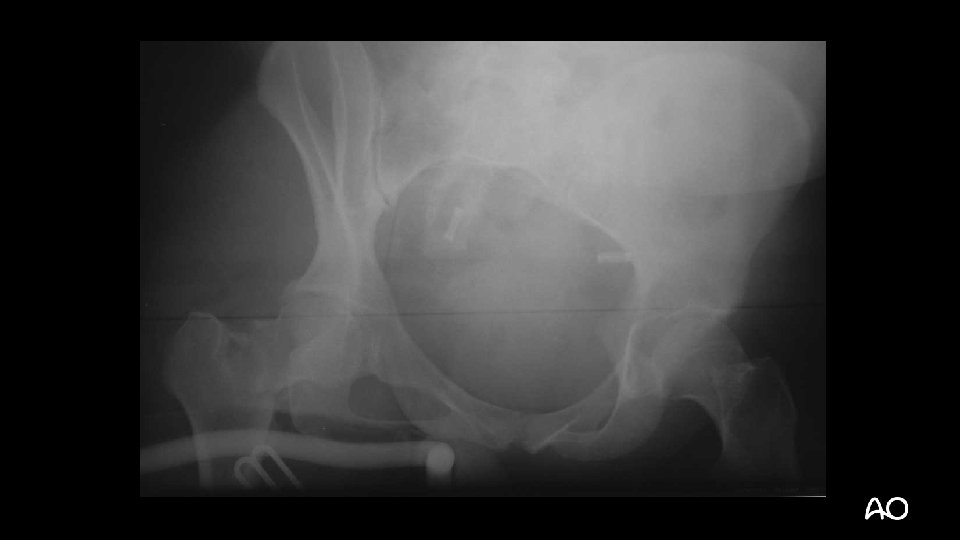

35 -year-old woman, motorcycle accident • Isolated right lower limb trauma • ABC’s – ok • No other injuries

• Closed fracture • Neurovascular status normal • No compartment syndrome

Displaced intracapsular femoral neck fracture Closed complex segmental femoral shaft fracture Closed simple articular supracondylar fracture Open (IIIa) bending wedge tibial shaft fracture

Displaced intracapsular femoral neck fracture Closed complex segmental femoral shaft fracture Closed simple articular supracondylar fracture Open (IIIa) bending wedge tibial shaft fracture 3 1 B 3 3 2 C 3 3 3 C 1 4 2 B 3

Displaced intracapsular femoral neck fracture 31 -B 3 Closed complex segmental femoral shaft fracture 32 -C 3 Closed simple articular supracondylar fracture 33 -C 1 Open (IIIa) bending wedge tibial shaft fracture 42 -B 3 (Local) damage control or early total care? Which injury to manage first?